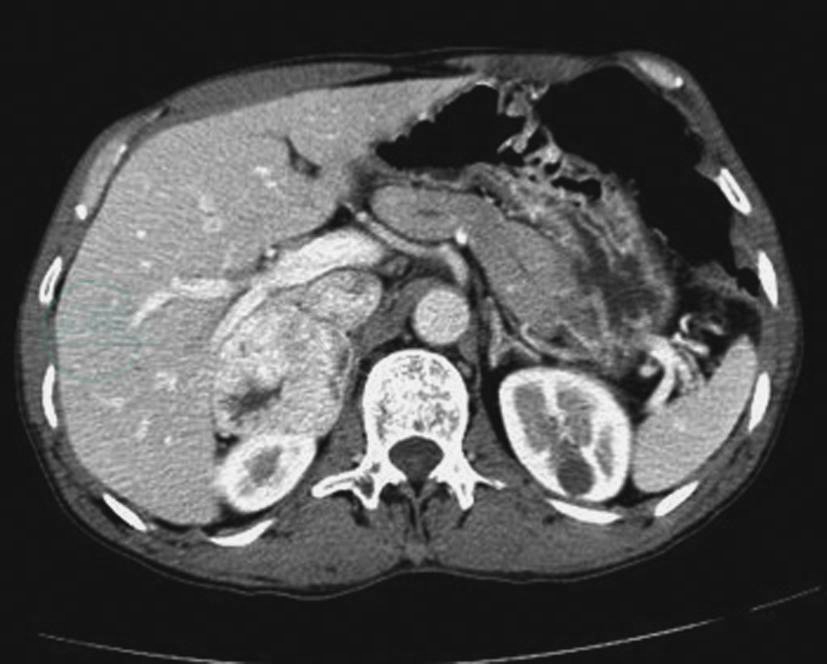

增强:瘤体内细胞团间有丰富血窦,增强扫描动脉期实性成分强化方式可类似脾脏,呈花斑状改变。静脉期及延迟期出现中度及以上强化,且呈持续强化(图11)。有学者用动脉期≥110.0Hu作为诊断嗜铬细胞瘤的标准,敏感性和特异度分别为58%和100%。由于瘤体血供丰富,生长过快,瘤体越大,其内越易引供血不足,出现缺血坏死、囊变,囊变可以呈各种形态,如边缘弧形、裂隙状、小圆形坏死、中央-边缘不规则坏死等。部分瘤体可以完全囊变而类似厚壁囊肿(图8,图12、图13),坏死边缘多锐利、平直。恶性嗜铬细胞瘤可见包膜和肾脏浸润,周围淋巴结及远处转移。强化均匀的嗜铬细胞瘤易与乏脂性腺瘤混淆。

图12嗜铬细胞瘤边缘裂隙状坏死

CT增强扫描门脉期示右侧肾上腺明显强化瘤体,其内见裂隙状无强化坏死区